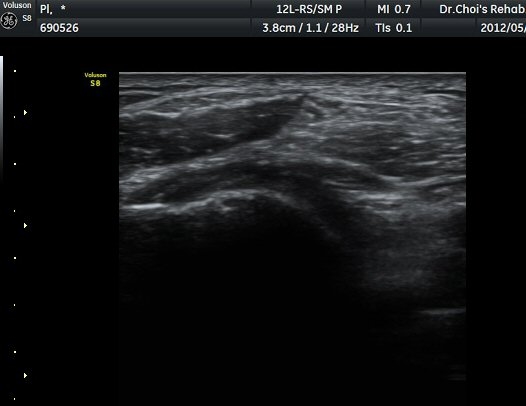

À­´Ù¸®(thigh) ¾Æ·¡ ºÎÀ§ ¿ÜÃø Ⱦ´Ü¸é°Ë»ç¿¡¼­ À̵ιڱ٠³»Ãø¿¡¼­ ÃѺñ°ñ½Å°æÀÌ Á¤»óÀûÀ¸·Î °üÂûµÈ´Ù(±×¸² 1, 2).